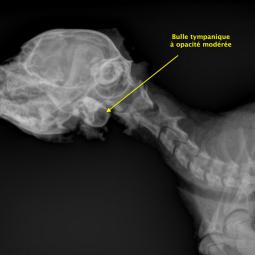

La trépanation de la bulle tympanique:

Cette technique chirurgicale consiste à perforer la paroi de la bulle tympanique et nettoyer son contenu. La chirurgie est nécessaire lors d'otite moyenne (accumulation de liquide dans la bulle tympanique) qui ne régresse pas avec un traitement médical.

Le diagnostic peut se faire par radiographie (cf images joints) mais l'examen de choix reste le scanner ou l'IRM si on souhaite une exploration fine de l'oreille interne.

A noter que les images présentes ici sont celles d'un chaton qui présente une otite moyenne droite modérée qui a été soignée à l'aide d'un traitement anti-inflammatoire et antibiotique.

Radio rostrale pour l'exploration des deux bulles tympaniques

Radio de profile pour l'exploration de la bule tympanique droite